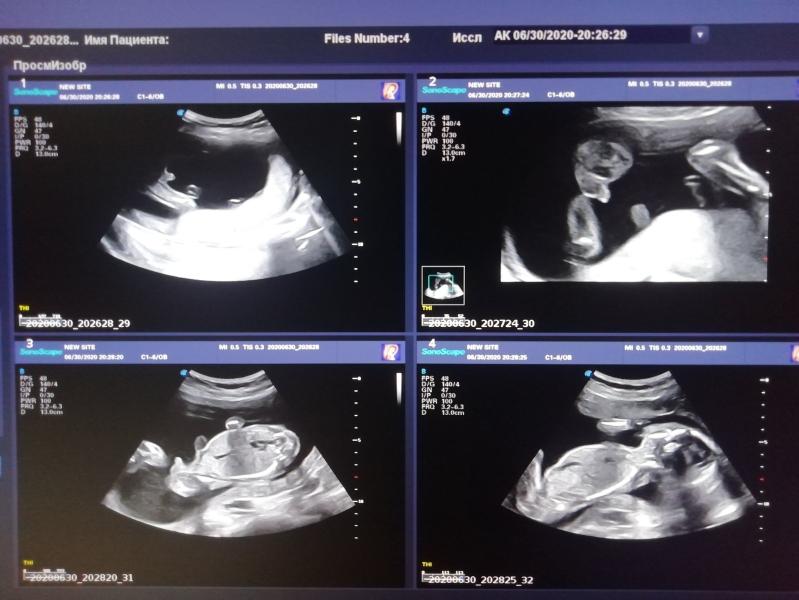

Сходили вчера платно с мужем узнать пол малыша) вообще я думала, что на втором скрининге скажут кто же там у нас, как это было три года назад, но нет.

Сразу после скрининга давай искать куда прям сегодня можно сходить узнать пол, иии нашла!

Панацея. Днём записалась, вечером пошли)

Пришли, я легла) узистка начинает меня смотреть, и спрашивает у нас - какие предположения у вас?

Я - девочка

А муж в этот момент смотрит в монитор и головой матает, и тут я понимаю... Нет, н...